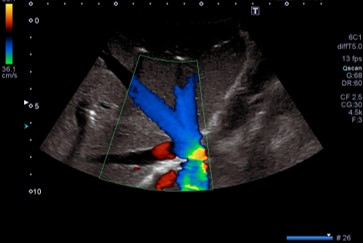

Konventionelle Sonografie

Farbkodierte Duplexsonografie

Ultraschalluntersuchungen der Gefäße